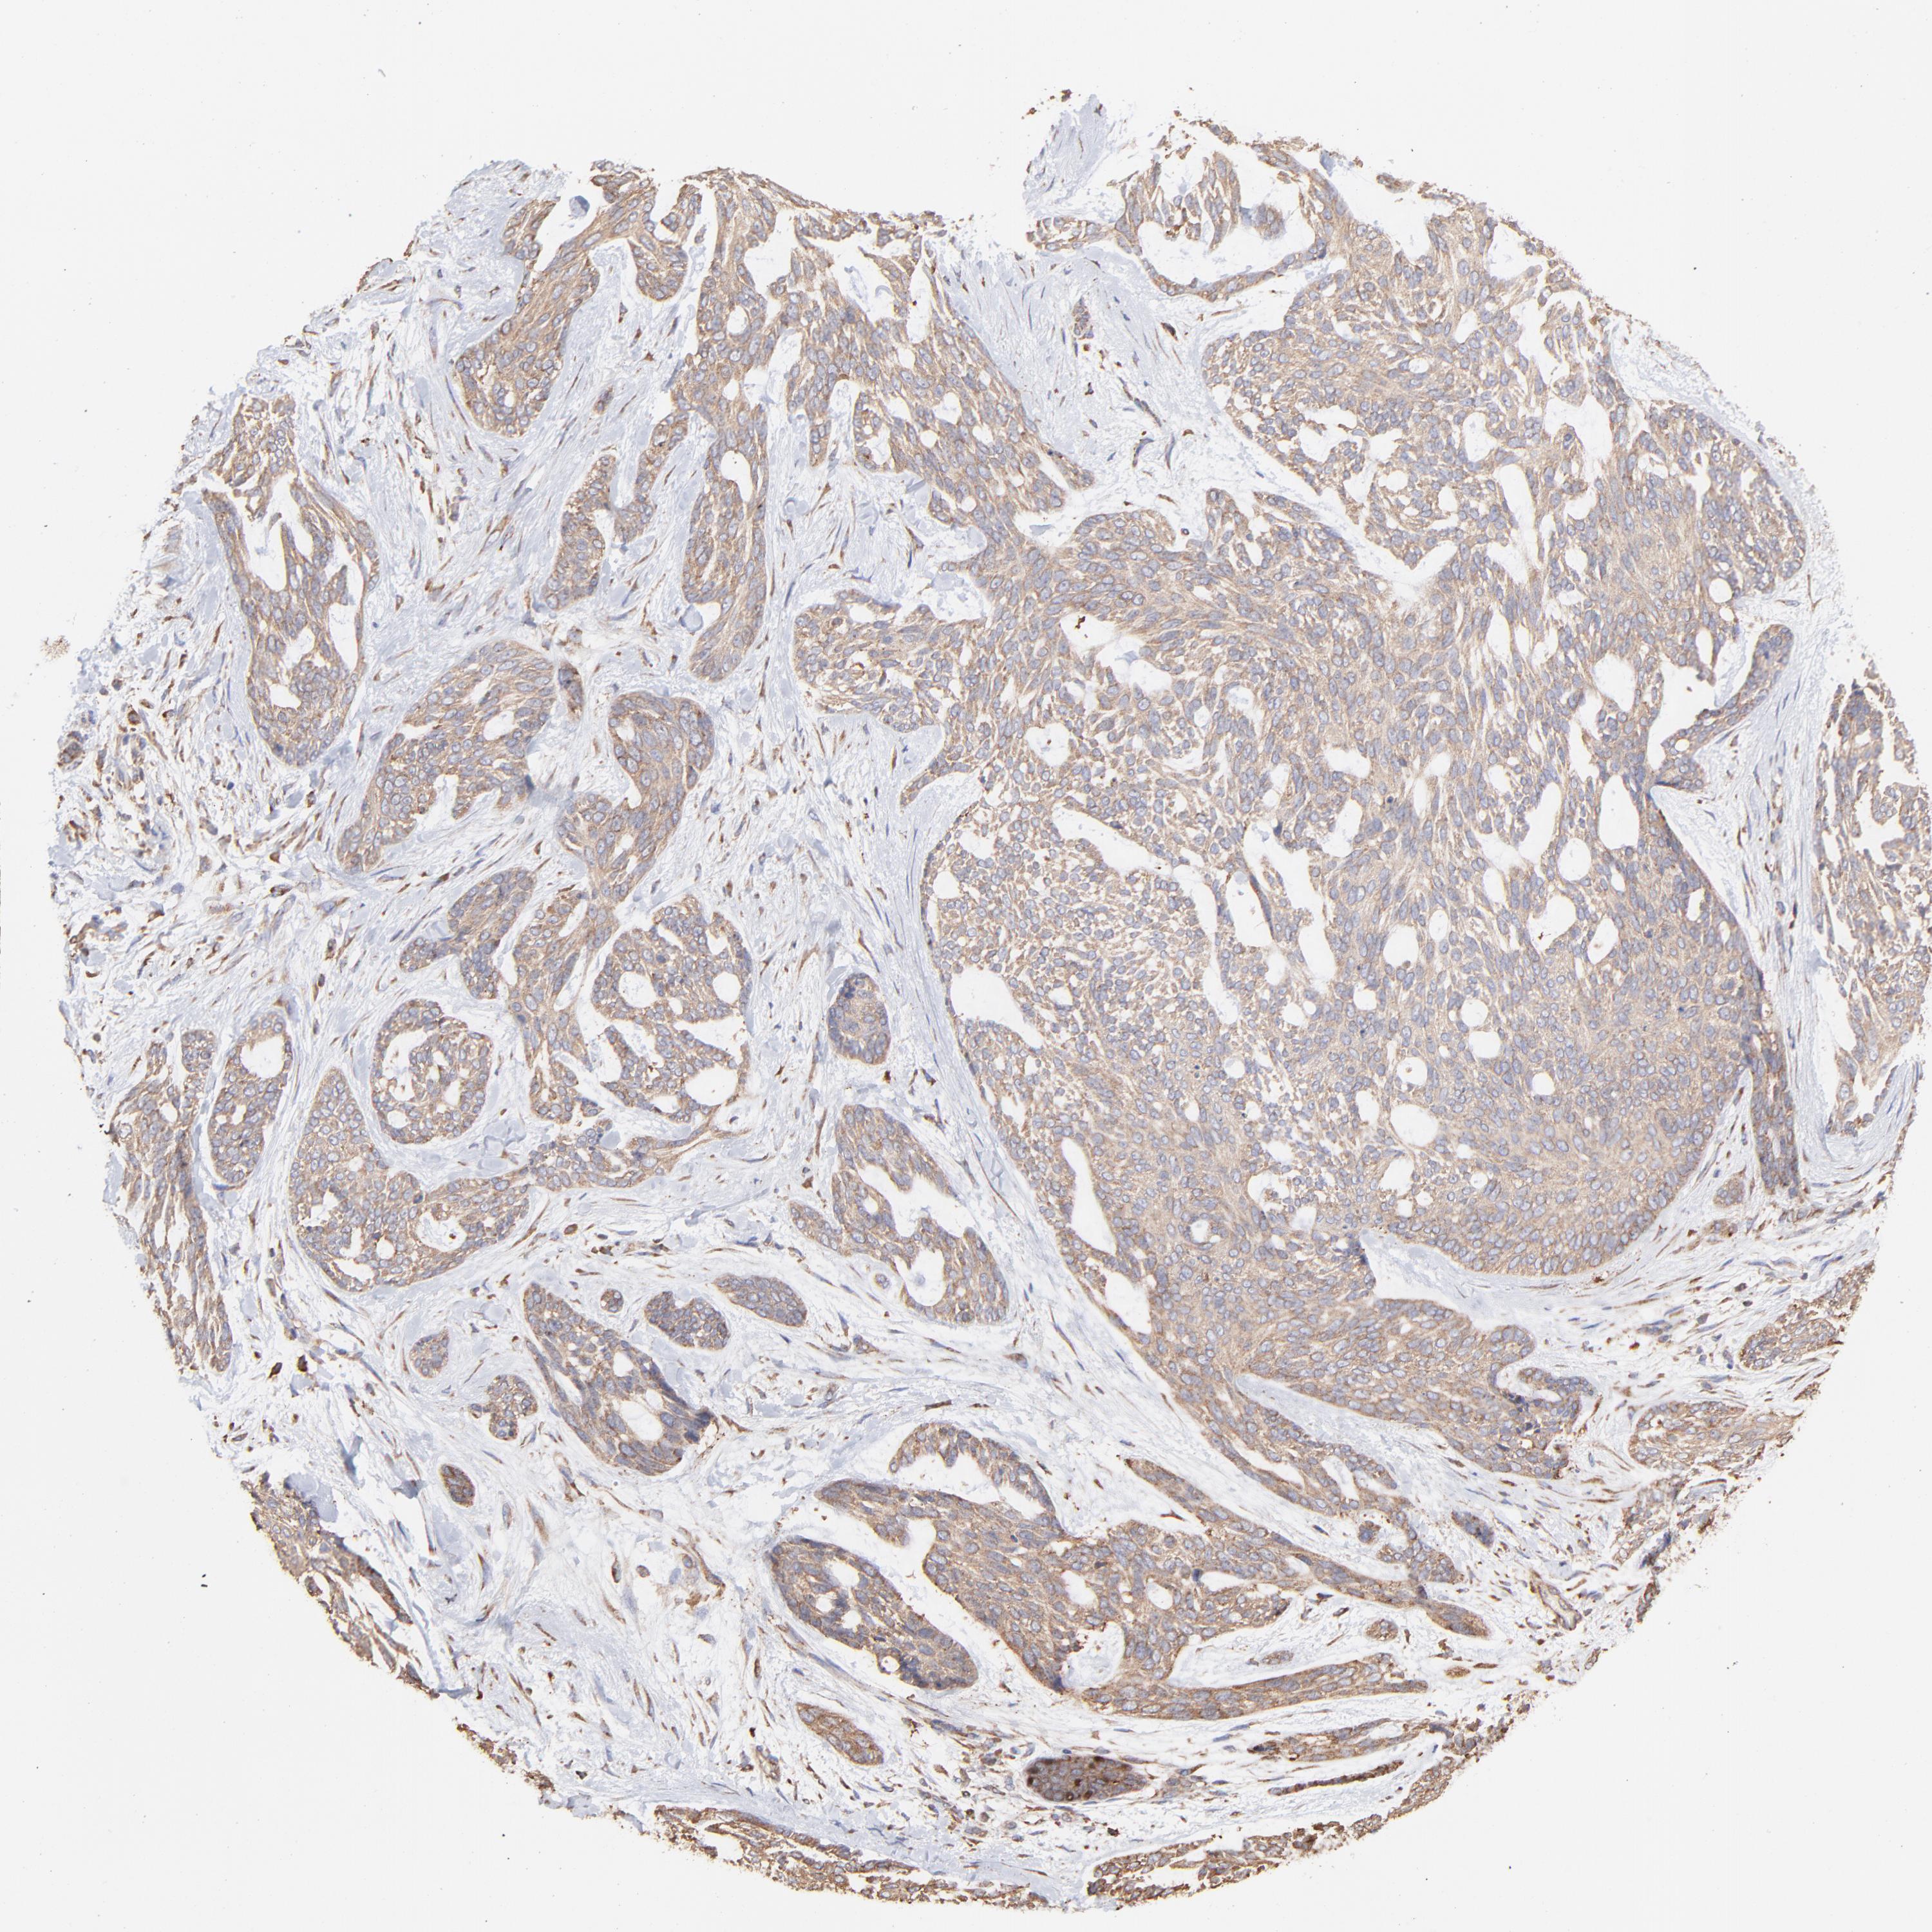

Basal cell and squamous cell cancer

SKIN CANCER - Protein expressioni

A mouse-over function shows sample information and annotation data. Click on an image to view it in a full screen mode. Samples can be filtered based on level of antibody staining by selecting one or several of the following categories: high, medium, low and not detected. The assay and annotation is described here.

Antibody stainingi

Antibody staining in the annotated cell types in the current human tissue is reported as not detected, low, medium, or high, based on conventional immunohistochemistry profiling in selected tissues. This score is based on the combination of the staining intensity and fraction of stained cells.

Each image is clickable and will lead to virtual microscopy that enables deeper exploration of all samples and also displays staining intensity scores, fraction scores and subcellular localization as well as patient and tissue information for each sample.

Antibody HPA002117

Staining

High

Medium

Low

Not detected

Intensity

Strong

Moderate

Weak

Negative

Quantity

>75%

75%-25%

<25%

None

Location

Nuclear

Cytoplasmic/membranous

Cytoplasmic/membranous,nuclear

Basal cell carcinoma